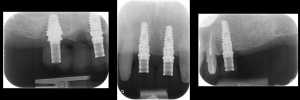

Periapical radiographs to verify the seat of the digital scan bodies. Fig. 12

Periapical radiographs to verify the seat of the implant- retained provisional restorations. Fig. 18